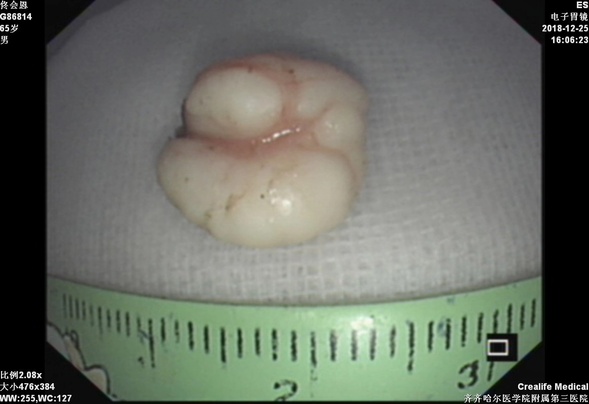

超声内镜下显示爱心形瘤体

剥离下来的病灶